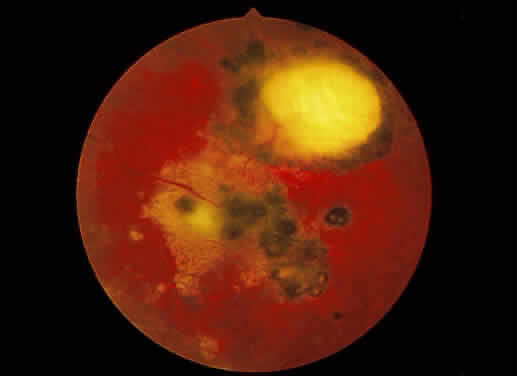

Fig. 13. A. Fundus photograph of a subpigment epithelium hemorrhage superotemporal

to the disc secondary to a macroaneurysm. Notice its dark color and sharp

border. The central portion of the hemorrhage has extended through

the sensory retinal to the subinternal limiting membrane area. B. Fluorescein angiography showing the retinal vessels overlying the deep

hemorrhage but obscured by the central extension anteriorly. (B, courtesy of William Tasman, MD, Philadelphia, PA) Fig. 13. A. Fundus photograph of a subpigment epithelium hemorrhage superotemporal

to the disc secondary to a macroaneurysm. Notice its dark color and sharp

border. The central portion of the hemorrhage has extended through

the sensory retinal to the subinternal limiting membrane area. B. Fluorescein angiography showing the retinal vessels overlying the deep

hemorrhage but obscured by the central extension anteriorly. (B, courtesy of William Tasman, MD, Philadelphia, PA)